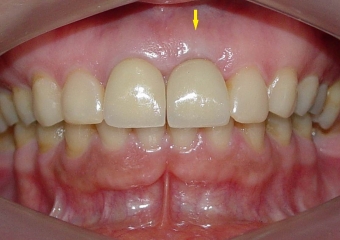

Prótese fixa em porcelana sobre implante Cone Morse